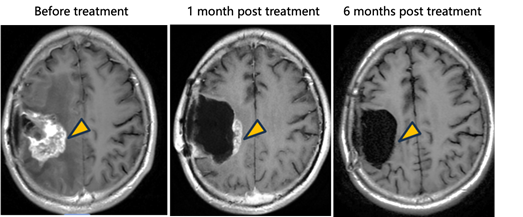

· Tumor Response: In the patient receiving intratumoral injection, a clear therapeutic response was observed, with target lesion shrinkage exceeding 90%.